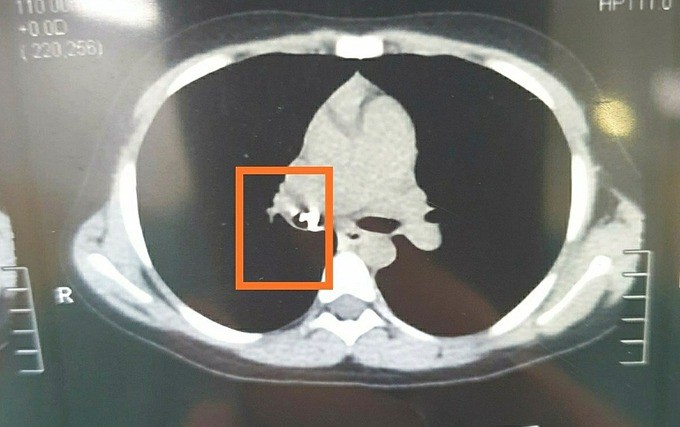

Mẹ đưa con đi khám, uống thuốc, vẫn không bớt ho. Đến bệnh viện tỉnh, bác sĩ chụp CT phát hiện dị vật cản quang giống chiếc răng trong phổi. Lúc này người mẹ mới nhớ các triệu chứng xuất hiện từ sau khi nhổ răng cho con tại nhà.

Bé được chuyển cấp cứu đến Bệnh viện Nhi đồng Thành phố (TP HCM) ngày 10/3. Bác sĩ chụp phim, xác định dị vật bít gần hoàn toàn phế quản gốc phải. Để lâu, dị vật có thể gây biến chứng khó lường như ứ khí viêm xẹp phổi, tràn khí màng phổi, nguy cơ nhiễm trùng viêm phổi nặng.